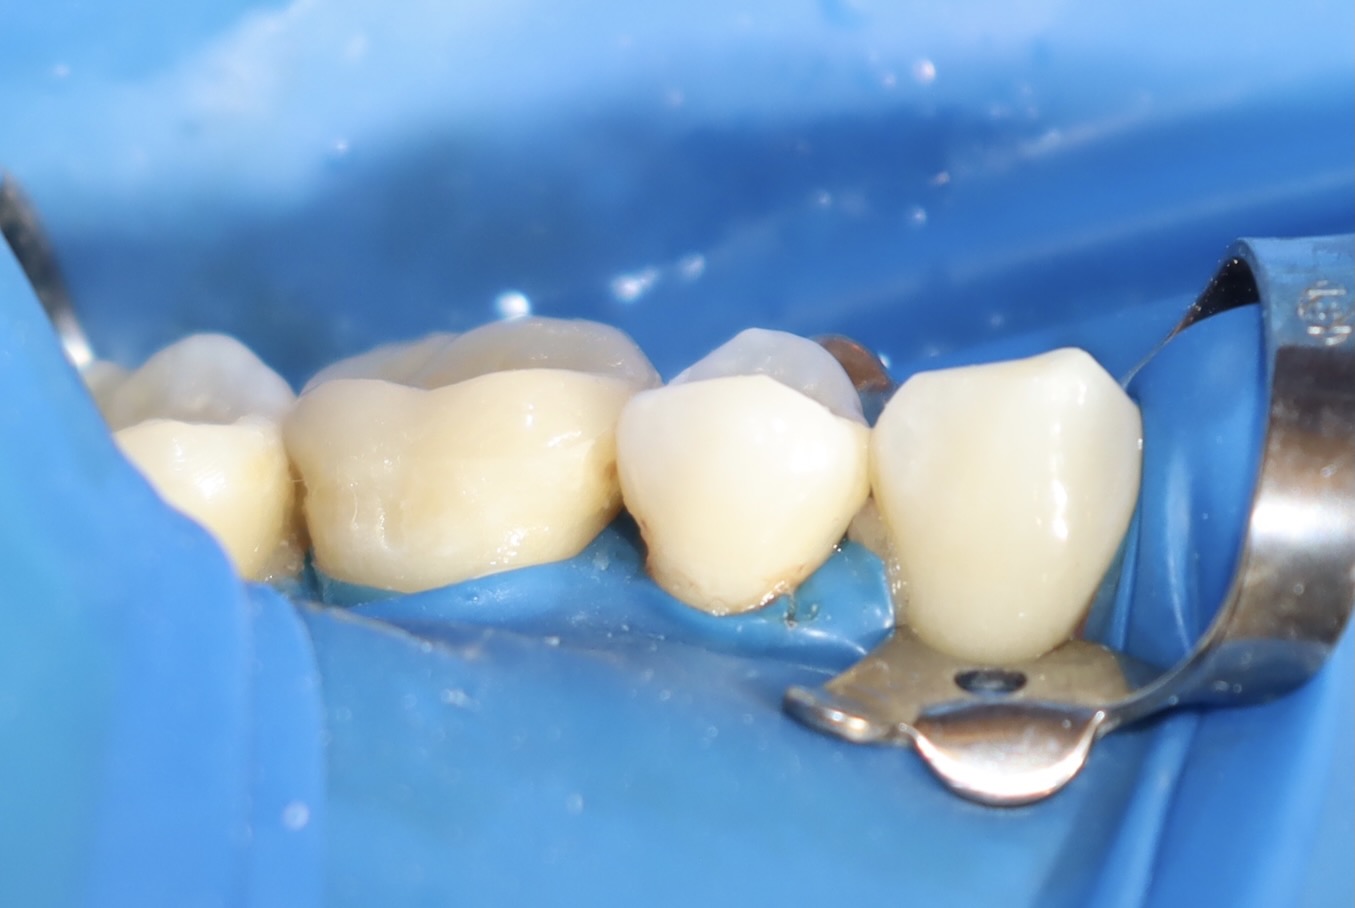

術中照片